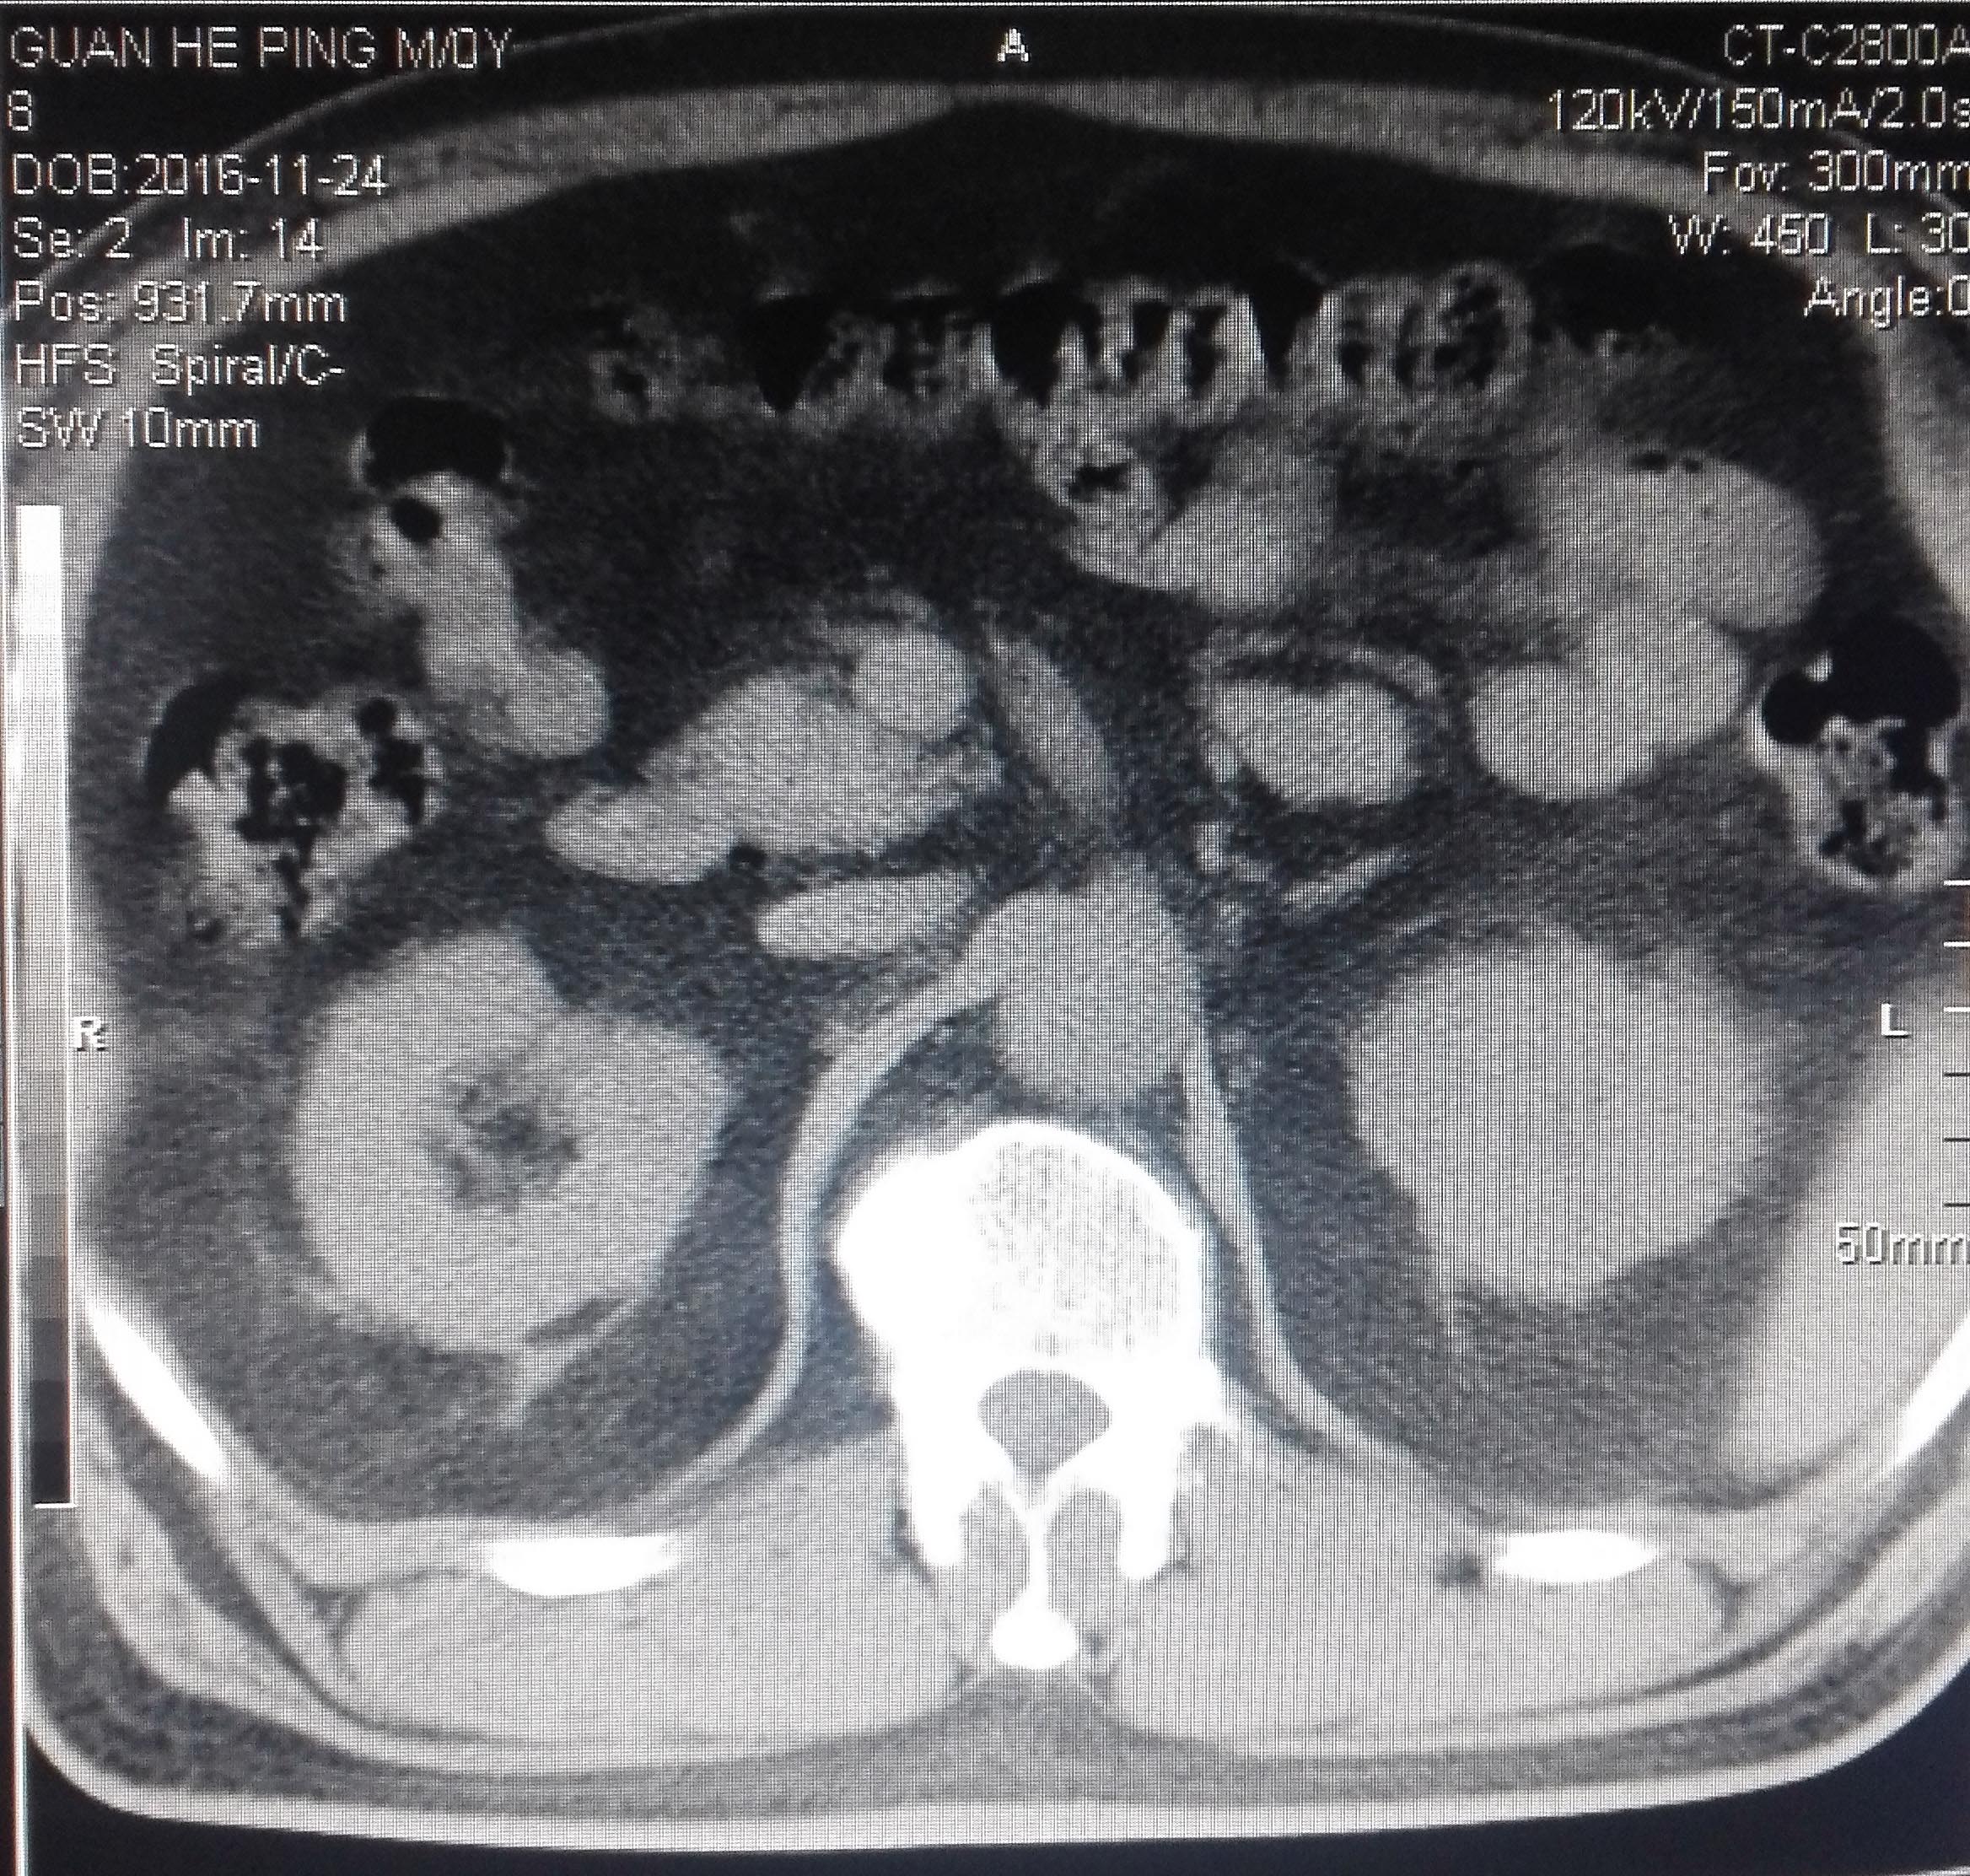

CT53065:男61岁 高血压病史多年

男61岁 高血压病史多年请各位老师帮忙看看左肾是囊肿?.B超报囊肿。

考虑左肾高密度囊肿可能,建议增强

左肾旁可见等密度外突隆起。边缘光整。考虑:左肾高密度囊肿可能。建议增强。

考虑高密度囊肿,但还要增强扫描来明确。